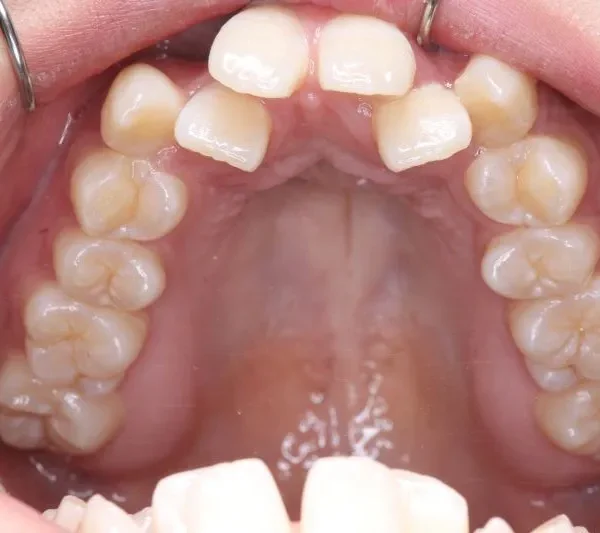

【大人の矯正】叢生・八重歯・交叉咬合・非抜歯症例・19歳女性【R.T様】

初診時年齢 19~29歳 (女性) 主訴 ガタガタ・交叉咬合が気になる

診断名 叢生・交叉咬合 装置名

矯正用アンカースクリュー4本・マルチブラケット矯正装置

抜歯の有無 非抜歯 治療期間・通院回数 3年 1ヶ月 / 42回

ガタガタ・八重歯を主訴に来院された患者様です。

初診